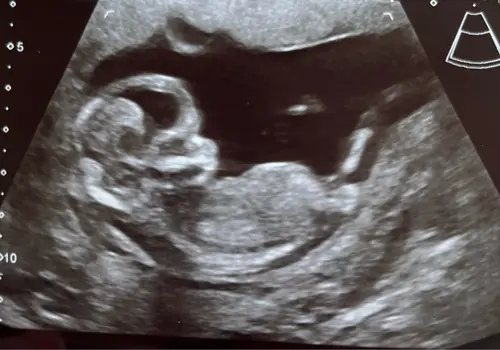

Iemand een idee? In de vorige topic 2x meisje 1x een jongentje werd er gezegd maar vandaag een nieuwe echo gehad bij de 13.4 weken vandaar nogmaals de vraag 😊

Reactie op Wensmoeder0546

Iemand een idee? In de vorige topic 2x meisje 1x een jongentje werd er geze ...

Geen nub te zien